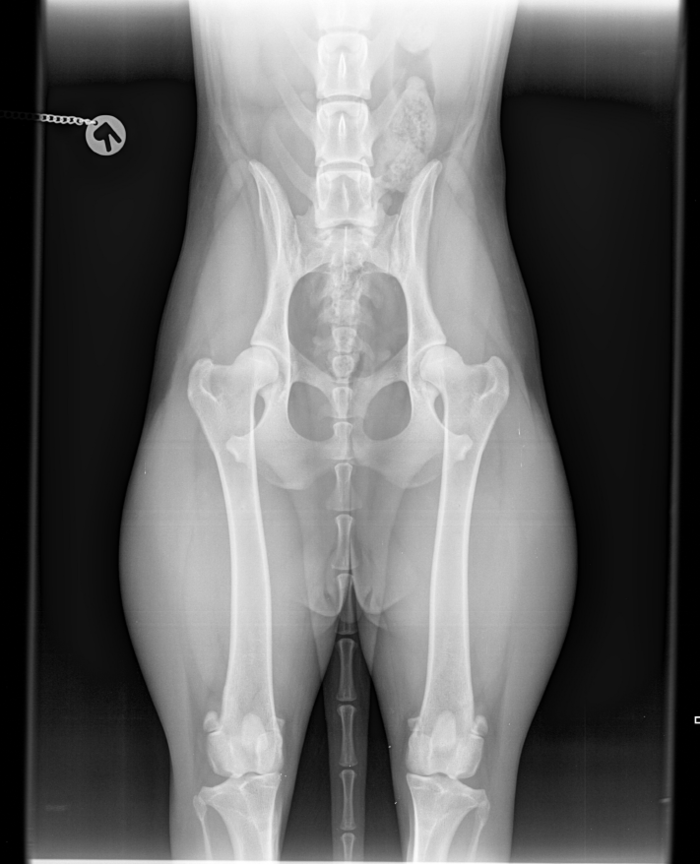

Orthopädie, Neurologie & Biomechanik

Diagnostik auf Klinik-Niveau. Vertiefen Sie Ihr Fachwissen in der objektiven Diagnostik und funktionellen Biomechanik. Von der computergestützten Ganganalyse bis zur neurologischen Rehabilitation – Sie erhalten evidenzbasierte Entscheidungshilfen für Ihre tägliche Praxis am Patienten.